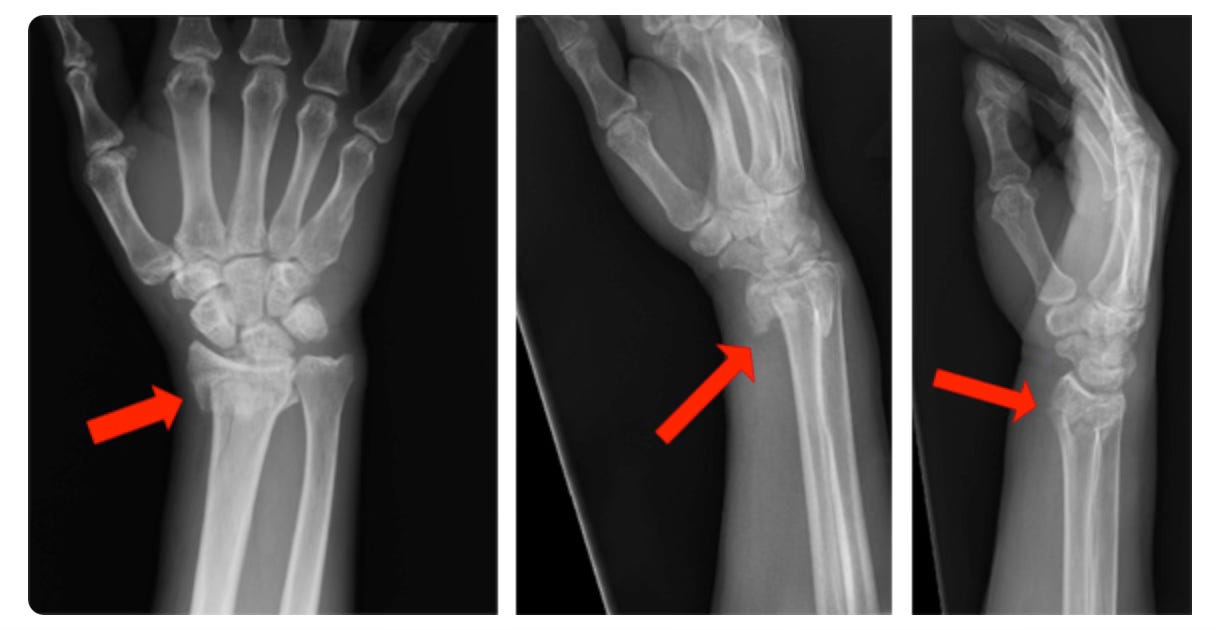

Dr Maria appeared at 9:00 to check on me. She explained that her associate, who had assisted with the surgery, would see me the next day at the VRSA clinic. She had completed her discharge papers, and as soon as the nurse removed the IV from my arm, I was free to go. She also provided me with the photo above. I called Denise, and within 2 hours, I was home again.